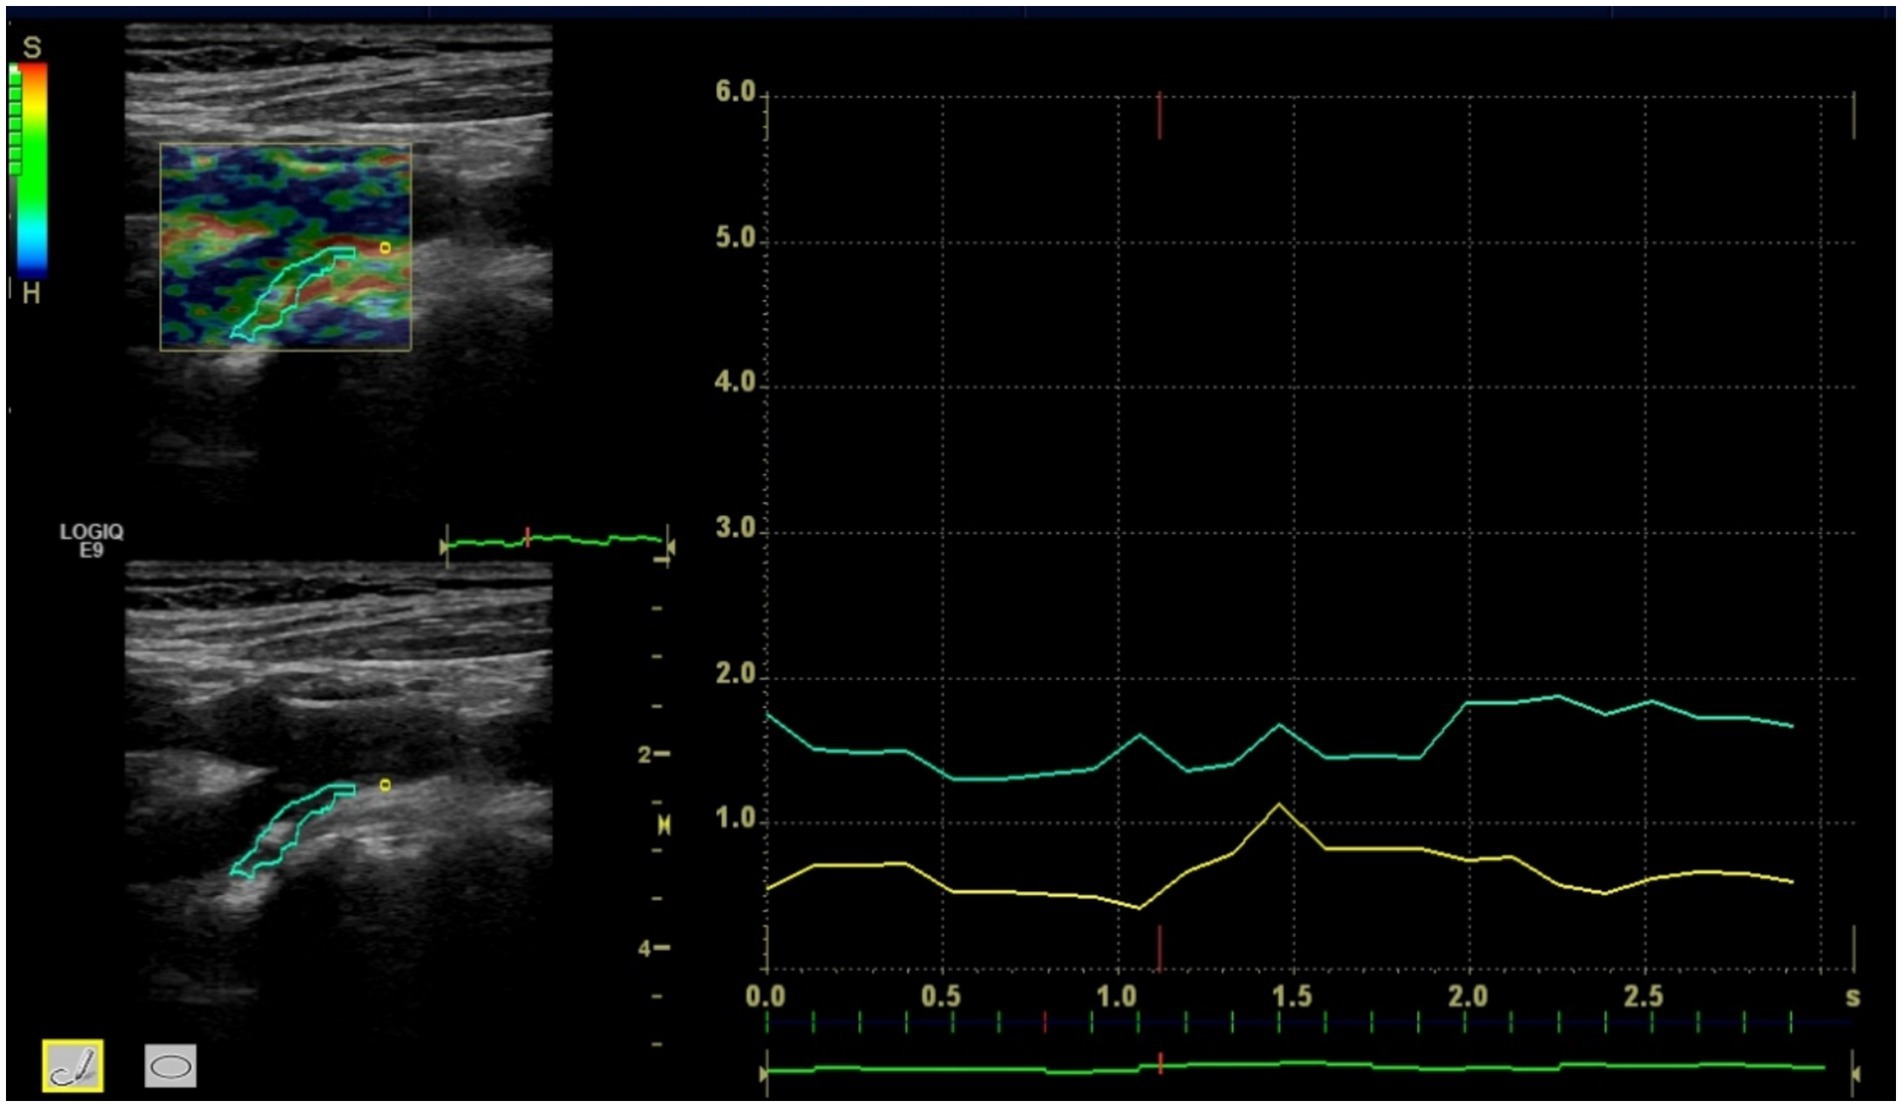

Ultrasound strain elastography of carotid plaques revealed that plaques predominantly exhibited yellow-green or green color coding (Figure 1), while the arterial walls were predominantly coded as red. Comparison of plaque strain elastographic characteristics between the deterioration and non-deterioration groups after cerebral infarction demonstrated that statistically significant differences was found in carotid plaque strain elastography value and plaque stiffness (p < 0.05). However, no statistically significant difference was found in arterial wall elasticity value (p > 0.05). See Table 3 for details.

Figure 1. The carotid plaque strain elastography showed plaque strain elastography value and arterial wall strain elastography value.

The basic principle of elastography is to apply an internal (including spontaneous) or external dynamic or static/quasi-static mechanical excitation to tissues. Under the physical laws of elasticity and biomechanics and so on. the tissues respond with certain changes in displacement, strain or velocity distribution, and so on. Common techniques include strain elastography and shear wave elastography, etc. (18) Studies have shown that soft plaques are lipid-rich, so they have low stiffness and high strain under compression, and mainly appear as yellow-green or green on elastographic imaging (19). In contrast, calcified plaques are lipid-poor and mainly composed of calcium, so they have high stiffness and low strain under compression and appear as blue. Mixed plaques are in between and present a mosaic pattern of blue and green.